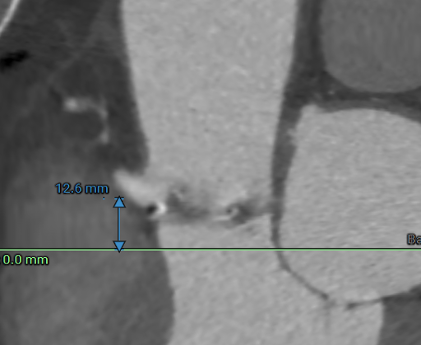

冠脉高度测量

LEFT CORONARY

左冠开口高度20.6mm

RIGHT CORONARY

右冠开口高12.6mm